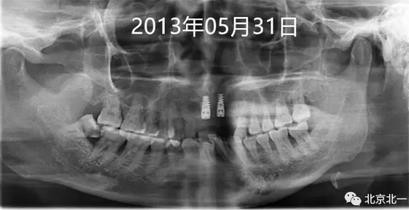

圖二:微創(chuàng)拔牙即刻種植當(dāng)天,采用ACTIVE 4.3*11.5,3.5*11.5(11 21位點)